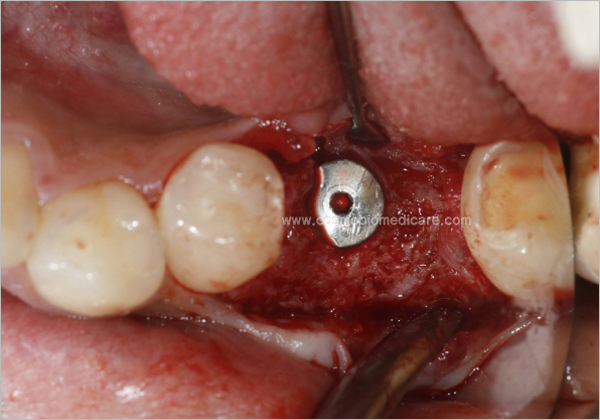

Clinical Cases

• Case1